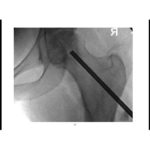

Surgical Dislocation of Hip

Courtesy: Dr Thiago Busato MD, Hip Surgeon, Curitiba, Brazil